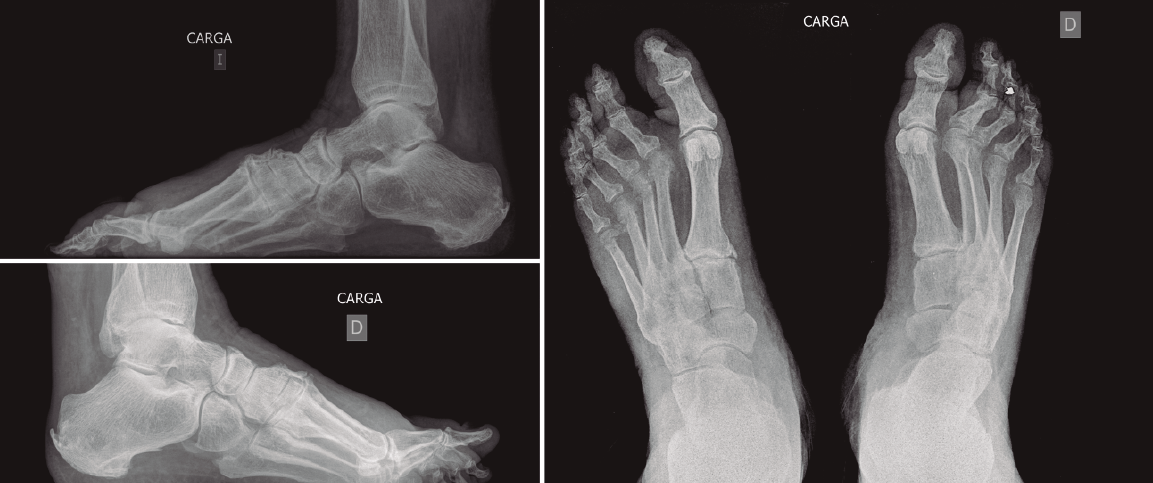

Figura 3. Imágenes radiológicas preoperatorias en carga. Pie derecho con lesión.